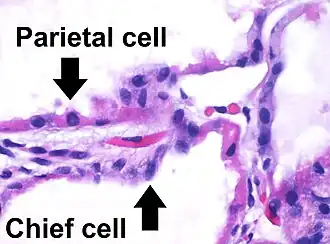

Human chief cells near tip of RED pointer | |

A gastric chief cell, peptic cell, or gastric zymogenic cell is a type of gastric gland cell that releases pepsinogen and gastric lipase. It is the cell responsible for secretion of chymosin (rennin) in ruminant animals and some other animals.[1] The cell stains basophilic upon H&E staining due to the large proportion of rough endoplasmic reticulum in its cytoplasm. Gastric chief cells are generally located deep in the mucosal layer of the stomach lining, in the fundus and body of the stomach.[2][3]

Gastric chief cells are epithelial cells which are found within the gastric unit or gastric gland, and form the base of the gastric unit.[11] The gastric chief cell has an extensive network of lamellar rough endoplasmic reticulum organized around the nucleus. The gastric chief cell also contains many large secretory vesicles filled with digestive enzymes in the apical cytoplasm.[12]